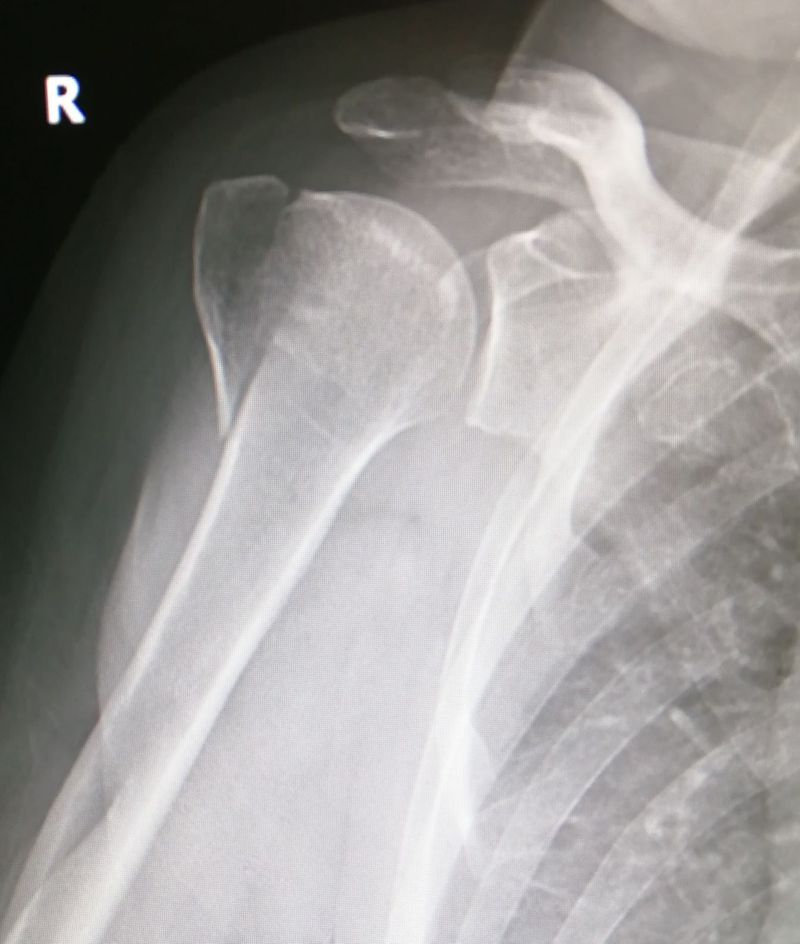

Right shoulder AP view

Fracture of the greater tuberosity.